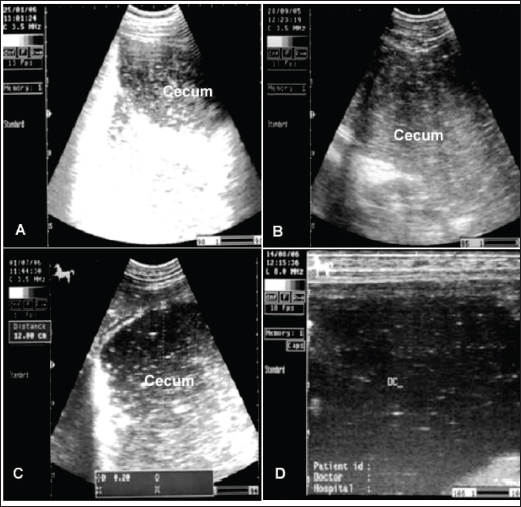

The cecum of horses with flatulent colic appears thin-walled due to gas distension; absence of sacculations; hypomotility on real-time ultrasonography, and the gases in the cecum prevent visualization of the ingesta inside the cecum (Le Jeune and Whitcomb, 2014). In comparison to healthy horses, the cecum is identified by its sacculations and contractions. The left ventral colon appears with a thin echogenic wall, the absence of sacculations, and the gases inside hinder the visualization of the ingesta. The right ventral colon compared to clinically normal horses shows the absence of sacculations and might be with thin or increased wall thickness, and this agrees well with Scharner et al., (2002), while in control horses it is characterized by the presence of sacculations, bright hyperechoic line, and the inability to identify the entire circumference of its wall (Fig. 5). Horses suffering from severe gas accumulation may collapse where postmortem examination confirms the diagnosis (Tharwat et al., 2008).

Fig. 5. Ultrasonogram of the cecum, left ventral colon (LVC), and right ventral colon (RVC) in 4 horses with flatulent colic. In A, the cecal wall appears echogenic in the absence of sacculations. In B, the LVC shows an echogenic wall with no sacculations. In C, the RVC shows a thin wall that appears echogenic in the absence of sacculations. In D, RVC appears in the absence of sacculations and with increased wall thickness. These organs contain a large amount of gas, which hinders their visualization.